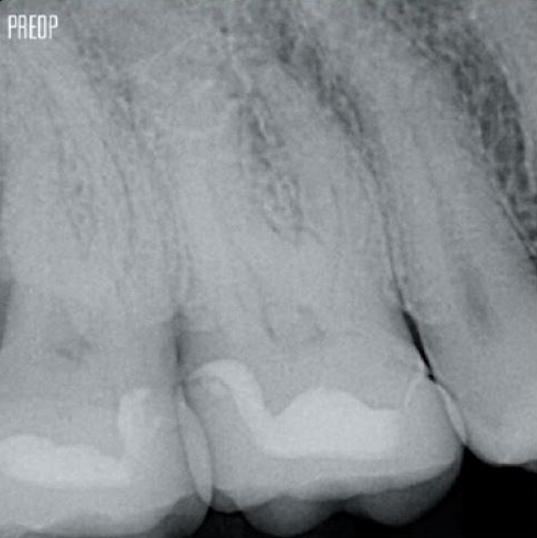

Photos gracieusement offertes par le Dr Ahmed Salman

La dentine de rétention constitue la base essentielle d’une restauration de qualité après un traitement de canal radiculaire. Plus la dentine est préservée au cours d’un traitement endodontique, plus il y a d’options pour réaliser une restauration réussie et durable1.

Une cavité endodontique conservatrice (CEC) est recommandée avec le système TruNatomy®.

L’accès est désormais possible sous différents angles alors que jusqu’à présent, il fallait sacrifier une structure (carie endodontique traditionnelle)1.

Pas besoin d’un accès en ligne droite1.

L’union de la géométrie de la lime, des cônes régressifs et du fil mince et très flexible permet un traitement efficace du traitement de canal tout en n’enlevant que la dentine là où c’est cliniquement nécessaire1.